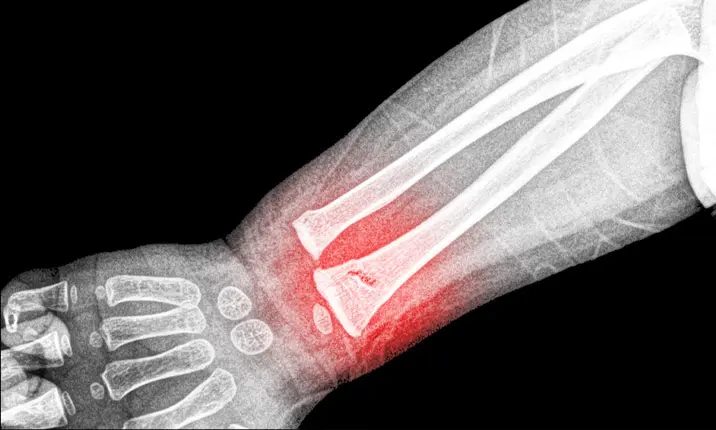

1. Wrist Fractures

Wrist fractures are the most common fractures in children. They typically happen when a child stretches out their hand to break a fall.

X-ray scans are used to assess the type of fracture sustained and if the growth plate is affected. The most common type of growth plate injury is a buckle fracture, where one side of the bone bends but does not break all the way through.